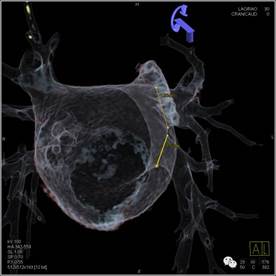

术前:测量肺静脉直径

左上肺静脉造影及融合